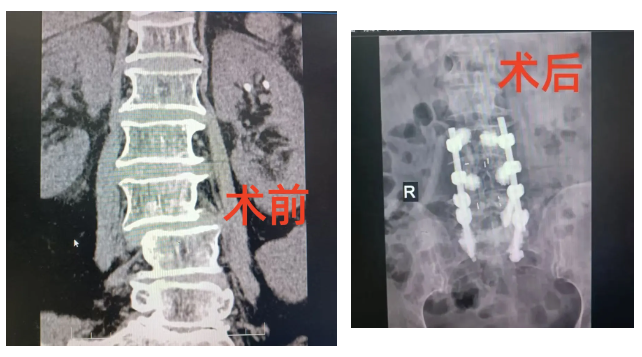

该患者因长期腰腿疼痛、间歇性跛行,行走距离日益缩短,严重影响生活质量。经详细检查,确诊为退变性腰椎管狭窄症伴脊柱侧弯。患者脊柱结构复杂,神经受压严重,保守治疗效果有限,手术指征明确。我院脊柱外科团队进行了深入细致的术前讨论,制定了周密的手术方案。

由于手术复杂,为确保手术安全,达到预期效果,特邀请上级医院专家来院指导,我院脊柱外科团队在专家指导下成功为患者实施了手术,有效解除了脊髓与神经根的压迫,重建了脊柱的稳定性。